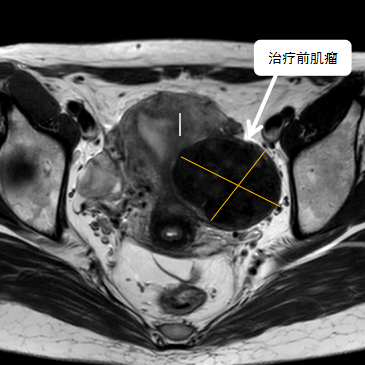

術(shù)前影像資料

經(jīng)過(guò)兩個(gè)月的藥物預(yù)處理,完善術(shù)前準(zhǔn)備,治療當(dāng)天陳主任帶領(lǐng)團(tuán)隊(duì)在3.0T磁共振清晰圖像引導(dǎo)下對(duì)子宮肌瘤進(jìn)行精準(zhǔn)消融,患者全程清醒,沒有明顯疼痛,經(jīng)過(guò)1個(gè)多小時(shí)的精細(xì)操作,手術(shù)非常成功,消融率接近90%,內(nèi)膜未見損傷!觀察一個(gè)小時(shí)后患者即自行回家。

術(shù)后即刻行增強(qiáng)磁共振檢查,顯示病變被消融近90%,內(nèi)膜未見損傷